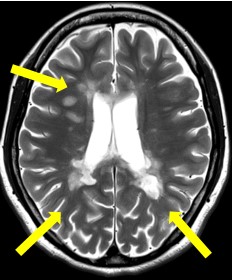

多発性硬化症(MS) 慢性炎症性脱髄性多発神経炎(CIDP)

脱髄性病変 T2協調像 腕神経叢のびまん性の腫大 STIR画像

神経核内封入体病(NIID) 海馬硬化症

大脳の皮髄境界の高信号域 海馬の萎縮と高信号 T2強調像